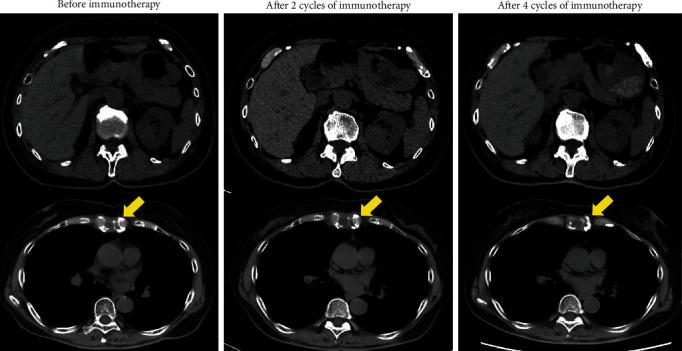

Collecting duct carcinoma (CDC) is a rare, extremely aggressive form of renal cancer. Recently, immune checkpoint inhibitors (ICI), anti-programmed death-1 (PD-1) antibody, and anti-cytotoxic T lymphocyte-associated antigen 4 (CTLA-4) antibody were approved for use against metastatic renal cell carcinoma. We herein described two cases of metastatic renal collecting duct carcinoma treated with a combination immunotherapy consisting of nivolumab and ipilimumab. In the first case, which included a bone metastasis, the best response achieved was stable disease (SD) for one year. In the second case, which was accompanied by a lung metastasis, the best response achieved was a partial response. The outcome of these cases suggested that the combination of nivolumab and ipilimumab is effective against renal collecting duct carcinoma.

集合管癌(CDC)是一种罕见的、极具侵袭性的肾癌形式。最近,免疫检查点抑制剂(ICI)、抗程序性死亡-1(PD-1)抗体和抗细胞毒性T淋巴细胞相关抗原4(CTLA-4)抗体被批准用于治疗转移性肾细胞癌。我们在此描述了两例接受纳武单抗和伊匹单抗联合免疫治疗的转移性肾集合管癌病例。在第一例中,存在骨转移,最佳反应为疾病稳定(SD)持续一年。在第二例中,伴有肺转移,最佳反应为部分缓解。这些病例的结果表明,纳武单抗和伊匹单抗联合使用对肾集合管癌有效。